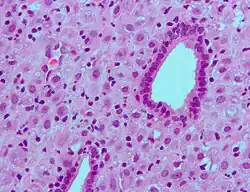

The decidua has a histologically-distinct appearance, displaying large polygonal decidual cells in the stroma. These are enlarged endometrial stromal cells, which resemble epithelium (and are referred to as "epithelioid").

Decidualization includes the process of differentiation of the spindle-shape stromal fibroblasts into the plump secretory decidual cells, which create a pericellular extracellular matrix rich in fibronectin and laminin (similar to epithelial cells).

Vascularity, as well as vascular permeability, is enhanced in the decidualizing endometrium.

Its leukocyte population is distinct, with the presence of large endometrial granular leukocytes being predominant, while polynuclear leukocytes and B cells are scant.

The large granular lymphocytes (CD56 bright) are called uterine natural killer cells| (uNK cells).